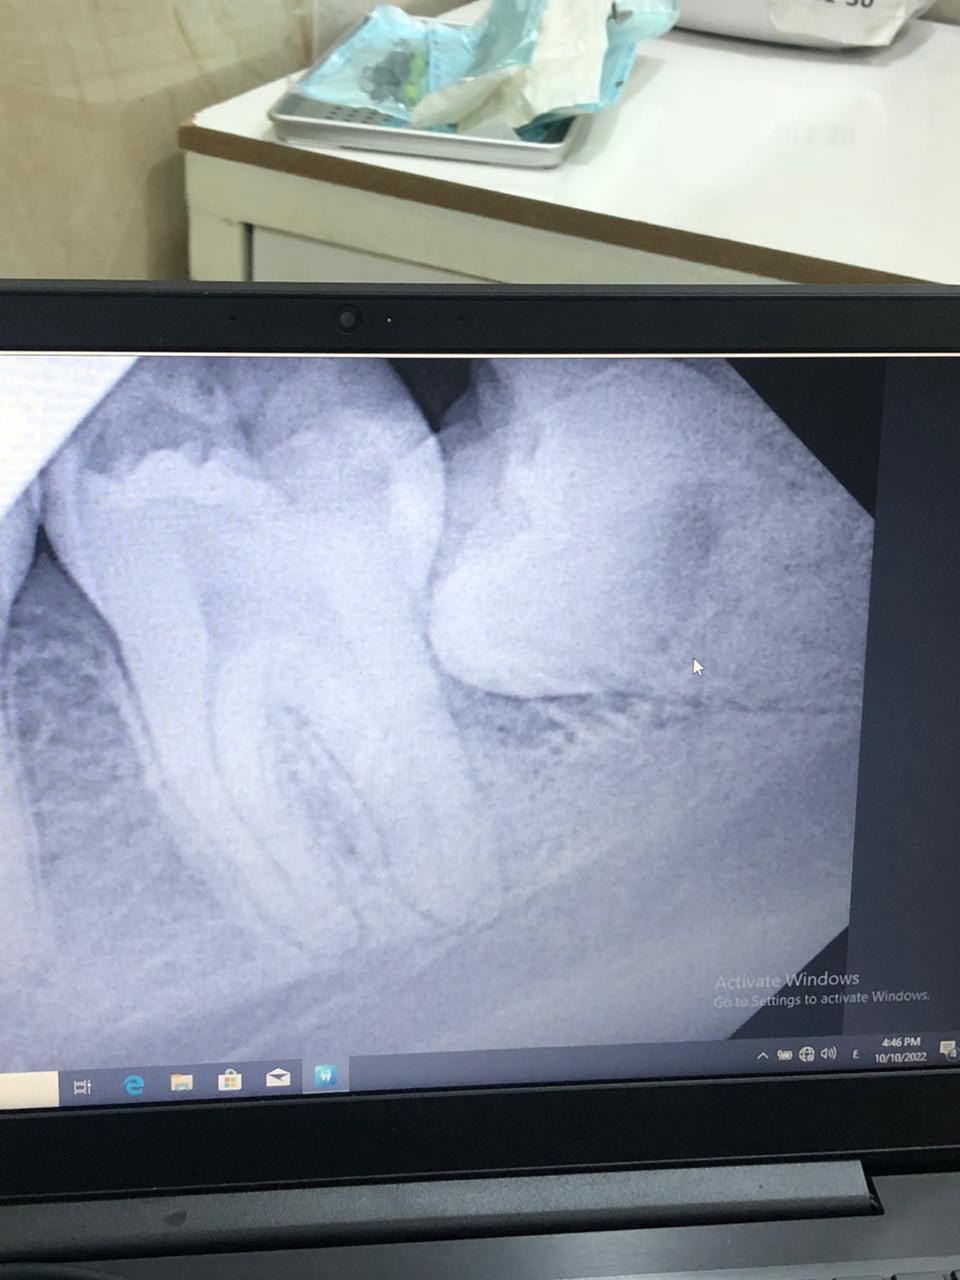

أجراء عمليات قلع جراحي في عيادة جراحة الأسنان

أجراء مجموعة من عمليات القلع الجراحي في عيادة جراحة الأسنان من قبل طلبة المرحلة الرابعة والخامسة وبأشراف الدكتور الأختصاص محمد علي شعلان والدكتور علي عادل والدكتور حسن خالد حسن حيث تم اجراء عمليات قلع مختلفة منها عملية قلع سن العقل .